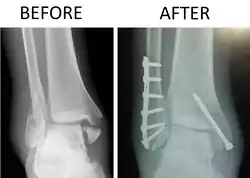

| X-ray of trimalleolar fracture repair before and after ORIF surgery | |

A trimalleolar fracture is a fracture of the ankle that involves the lateral malleolus, the medial malleolus, and the distal posterior aspect of the tibia, which can be termed the posterior malleolus. The trauma is sometimes accompanied by ligament damage and dislocation.[1]

Surgical repair using open reduction and internal fixation is generally required, and because there is no lateral restraint of the foot, the ankle cannot bear any weight while the bone knits. This typically takes six weeks in an otherwise healthy person, but can take as much as twelve weeks. Non-surgical treatment may sometimes be considered in cases where the patient has significant health problems or where the risk of surgery may be too great.[1]